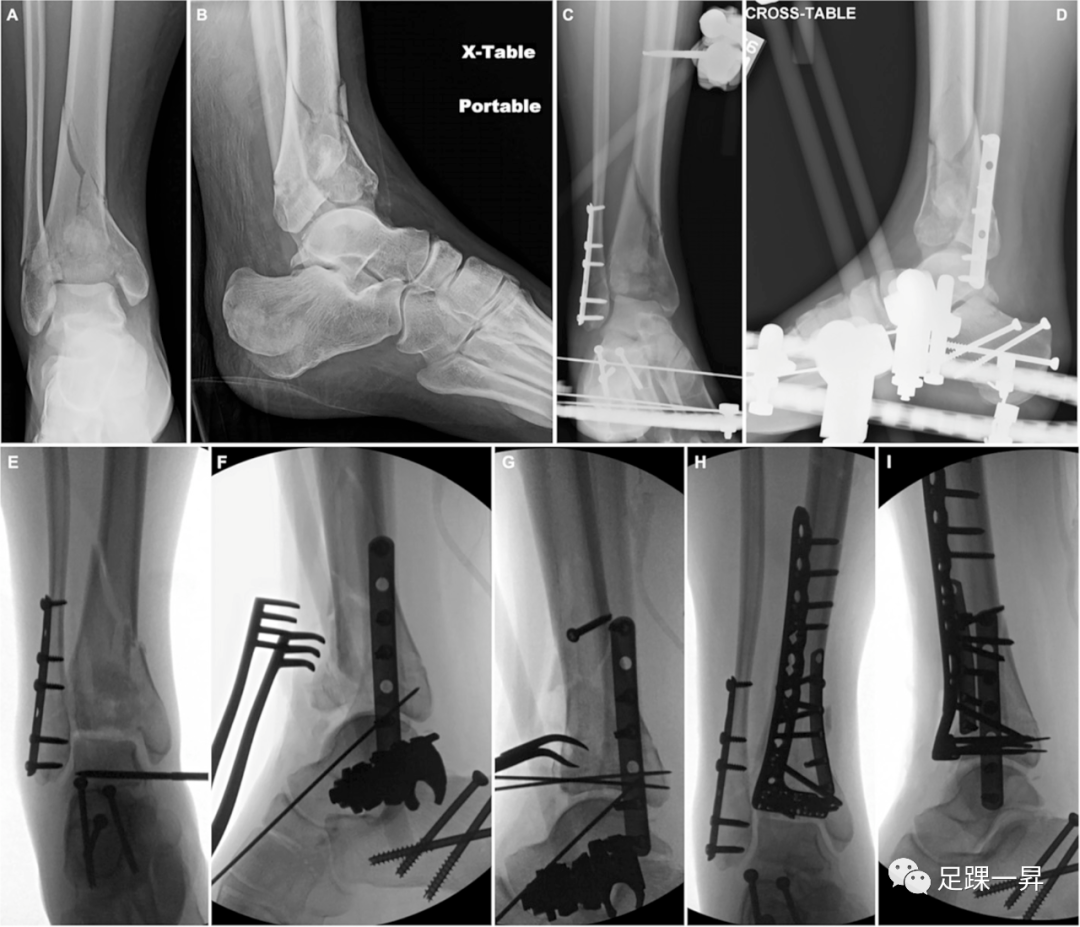

△图示Pilon骨折合并跟骨骨折。跟骨骨折的初始经皮复位和螺钉固定,而Pilon骨折初始采用临时外固定架和外踝骨折的钢板固定。二期Pilon骨折切开复位并予以钢板固定。